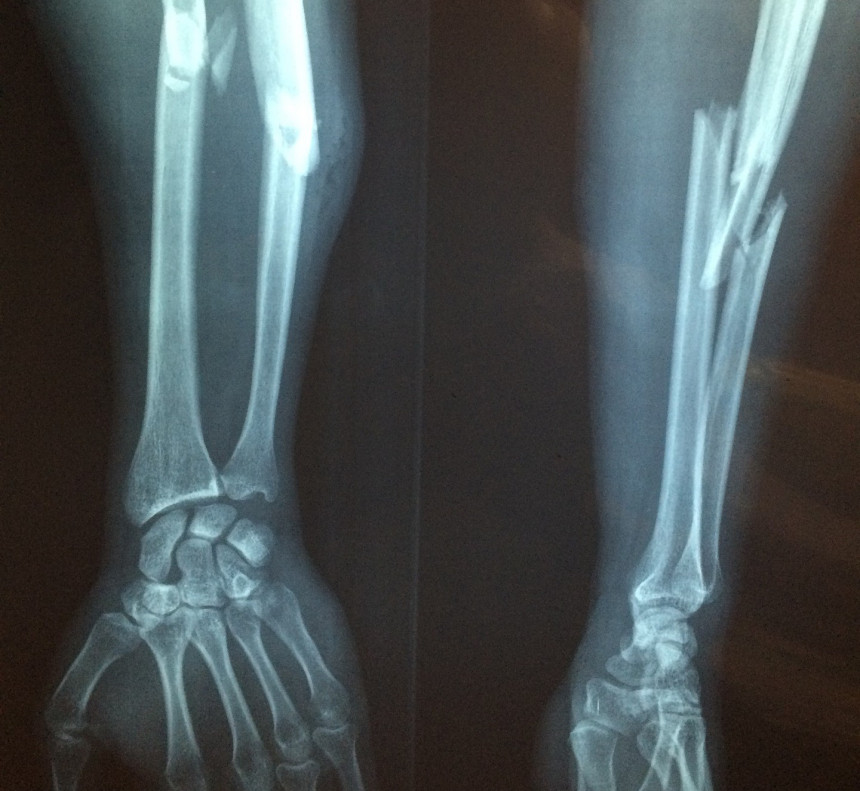

Google trends dati liecina, ka šodien Krievijā internetā visvairāk tika meklētas aviobiļetes uz tuvākajiem reisiem uz valstīm, kuru apmeklēšanai nav vajadzīgas vīzas, tāpat tika meklēta informācija par "mobilzāciju Krievijā", "mītiņu pret mobilizāciju", kā arī dažādi praktiski jautājumi, piemēram, "kā salauzt roku", "kā izbēgt no mobilizācijas".

Ekrānuzņēmums